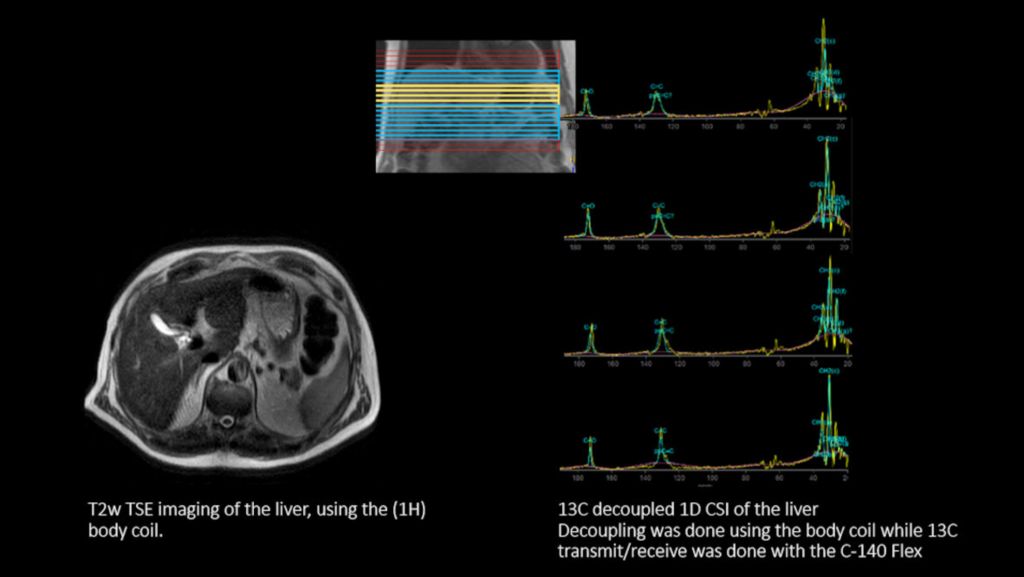

The transmit-receive C-140 flex coil, with a 14 cm diameter, allows to perform carbon (13C) imaging, spectroscopy and research studies, across all anatomies. Benefit from improved 13C signal-to-noise ratio (SNR) and simplified 13C spectra, by combining body coil decoupling with this transmit-receive surface coil. Workflow does not differ from proton imaging. 13C imaging and spectroscopy can be run and reconstructed directly from the standard user interface. The ExamCard interface immediately recognizes the C-140 flex coil. And the 13C nucleus is just a scan parameter like any other sequence parameter. Viewing of 13C images and spectra, as well as sending data to PACS, is fully integrated. Combined with our multi-nuclei specialist package, the transmit-receive C-140 flex coil delivers the confidence to explore new imaging pathways and the speed to integrate multi-nuclei studies in your day-to-day workflow.

4 Compared to non-decoupled spectroscopy results